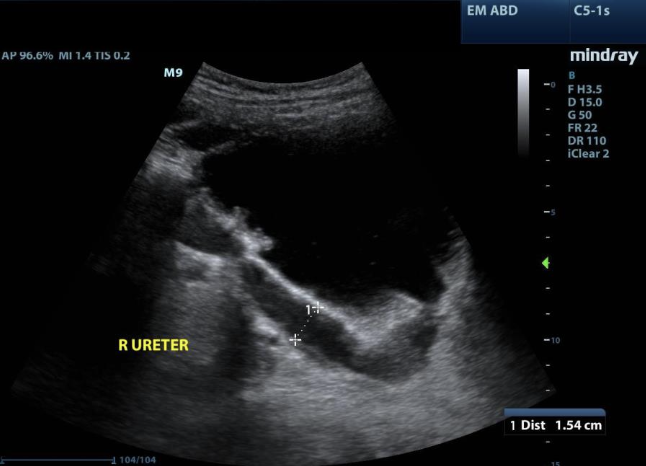

Hydroureter → dilation of the ureter from BOO, ureter mass, gravida uterus, uterine fibroid compression

clinical hx: pregnancy, BPH (older males), nephrolithiasis prone (pregnancy, stasis)

s/sx: renal colic, symptoms mimic UTI (frequency, urgency)

2D US: dilated ureter at UVJ

color doppler: avascular

DDX: